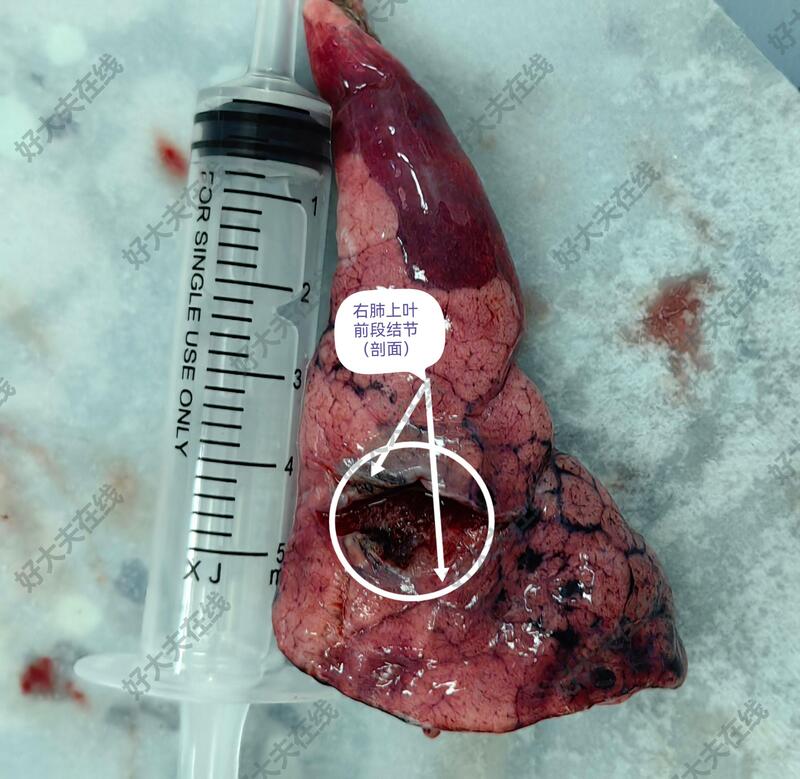

图1-5,女性,45岁,体检发现右肺上叶前段结节,亚实性(磨玻璃)结节、毛刺、分叶、胸膜牵拉等,短期随访结节不消散。胸腔镜微创手术切除,病理报告为肺浸润性腺癌。

例1,45岁,女性患者,病理报告系浸润性肺腺癌,建议完善基因检测,查找靶点,便于指导随访观察,目前,暂不考虑化疗等。